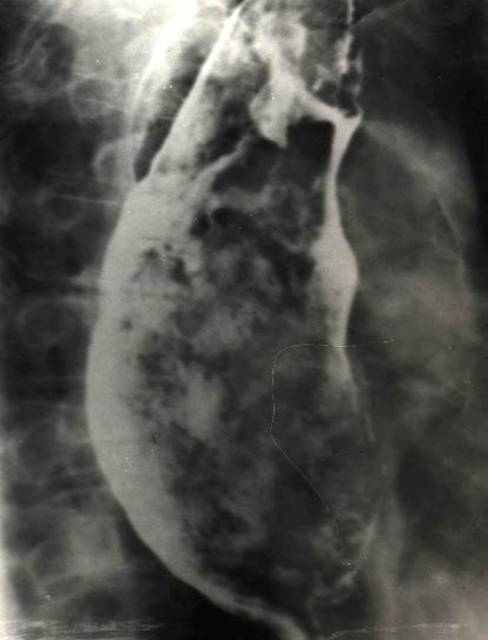

Ведущим методом диагностики рака пищевода является рентгенологический, который осуществляется при искусственном контрастировании пищевода водной взвесью химически чистого сернокислого бария различной консистенции. Выполняется также рентгенологическое исследование желудка, 12-перстной кишки. При исследовании вначале дают жидкую бариевую взвесь, в дальнейшем концентрацию вещества подбирают соответственно степени сужения просвета пищевода. Рентгенологическая картина рака пищевода зависит от размеров и формы роста опухоли. Рентгенологическими симптомами рака пищевода являются: нарушение структуры рельефа слизистой оболочки пищевода, отсутствие перистальтики стенки пищевода, дефект наполнения, наличие тени опухолевого узла. (рис. 1)

Рис. 1 Рентгенограммы пищевода больного Б. Рак верхне- и нижнегрудной части пищевода

Самым ранним и наиболее достоверным, но трудно выявляемым рентгенологическим признаком рака пищевода, является отсутствие перистальтики стенки пищевода на участке расположения опухоли. Несколько позже появляются и другие признаки злокачественного роста. Иногда это перестройка или разрушение рельефа слизистой оболочки, выражающаяся атипичной формой и расположением складок слизистой, бесформенными отложениями контрастного вещества. Чаще других симптомов выявляется дефект наполнения, размеры которого зависят от стадии развития опухоли. При распространенном процессе выявляется тень опухолевого узла, резкое сужение просвета пищевода до полной непроходимости его. Перфорация опухоли пищевода в прилегающие органы имеет типичную рентгенологическую картину. При образовании пищеводно-трахеального или пищеводно-бронхиального свища виден выход контрастного вещества за пределы органа и контрастирование бронхиального дерева. Для уточнения границ прорастания опухоли применяют компьютерную томографию.